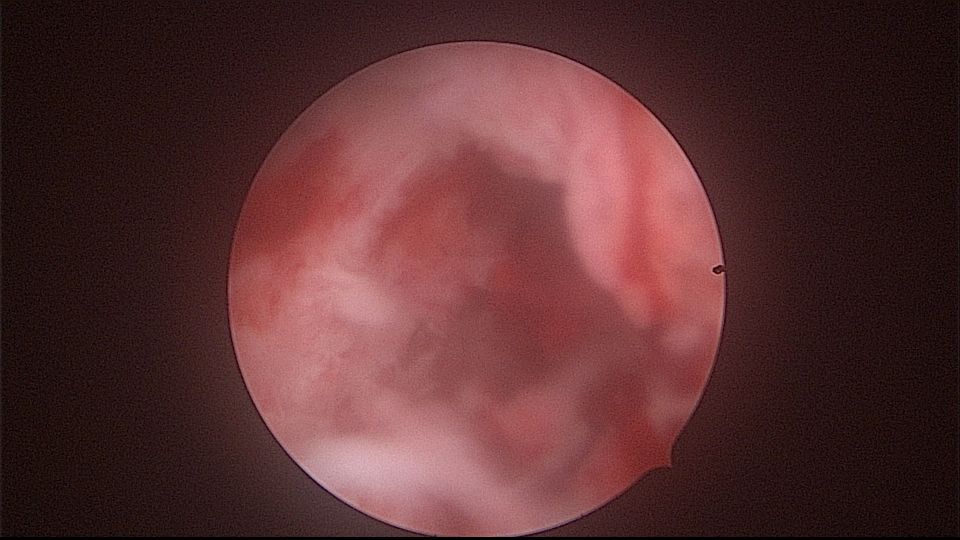

患者52岁,G2P1,顺产1次。安环27年,外院取环失败。病人肥胖,子宫极度前倾前屈位,宫腔镜见宫颈管组织杂乱,宫颈管上段右前壁见假道,膨宫不良,视野模糊,寻找宫腔方向困难,准备B超监护过程中,拆走扩阴器,腹部下压子宫,终于寻找到了宫颈内口,看到了爱母环下端,异物钳牵拉出节育环,再次探查宫腔,无其他异常。